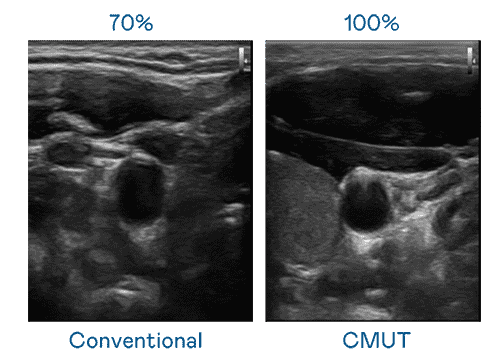

CMUT 技术是一种用电容式微机电元件来产生超音波讯号的技术。。。。与传统 PZT 压电式技术相比,,,,CMUT 频宽增加 30%,,,更宽频的超音波讯号让影像解析度大幅提升,,是实现高影像品质医疗超音波扫描、、促进精准医疗发展的关键技术。。。。

大频宽带来超清晰影像

超音波影像的解析度高低,,,首先取决于探头能发出的讯号频宽。。。欧陆注册 CMUT 可提供高清晰的超音波讯号,,,提供高频宽、、、、高灵敏度、、、、影像纹理细节更高的超音波影像,,,协助医护人员缩短影像判读时间及利用精准的医疗影像进行诊断。。。